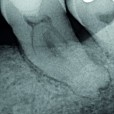

3/3 Post-operative x-ray Mesial canals: One Curve is used up to the first curvature, rinse. Second wave with One Curve  down to the apex. Distal canal: One Curve direct to the apex, NaOCl 5,25% then EDTA 17%, final rinse with NaOCl before obturation.